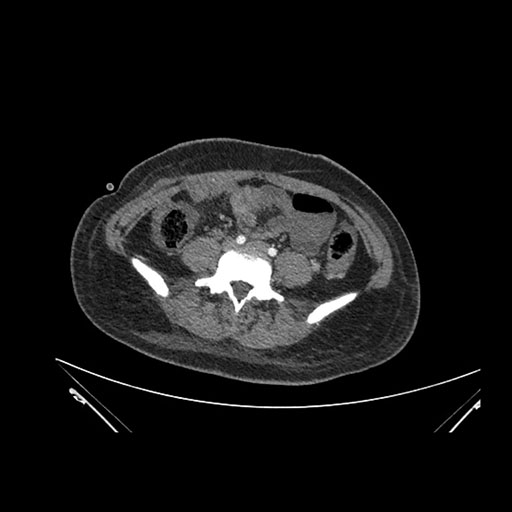

Imaging Analysis

Look through the patient's CT scan to identify any areas of concern for the necessary procedure.

Axial Venous

Based on initial findings, which issue(s) would you be most concerned about?